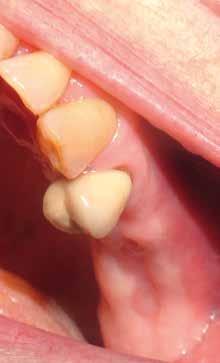

Deve prevedere sia l’osservazione sia la palpazione di tutte le mucose orali, partendo da labbra, lingua, guance, per arrivare alla valutazione del tessuto gengivale dei fornici, del palato e la gengiva aderente. Se ne devono valutare colore (fig. 11 ittero mucoso), fragilità, consistenza e presenza di ulcere o tumefazioni.

L’esame clinico rappresenta sicuramente la fase di analisi più complessa in quanto i parametri da valutare sono molti e possono interessare tutte le specialità odontoiatriche. Sono da valutare lo stato di salute della dentatura residua, la presenza o meno di manufatti protesici, il rapporto intermascellare,

lo stato di igiene orale, la condizione dei tessuti parodontali, le abrasioni dello smalto che ci indirizzino verso la diagnosi di parafunzioni come il bruxismo, la limitazione nell’apertura della bocca o la presenza di deviazioni per disordini temporo-mandibolari. (Figg. 16-21)

FIG. 17 FIG. 16 FIG. 19 FIG. 18 FIGG. 16-21: Valutazione FIG. 21 FIG. 20